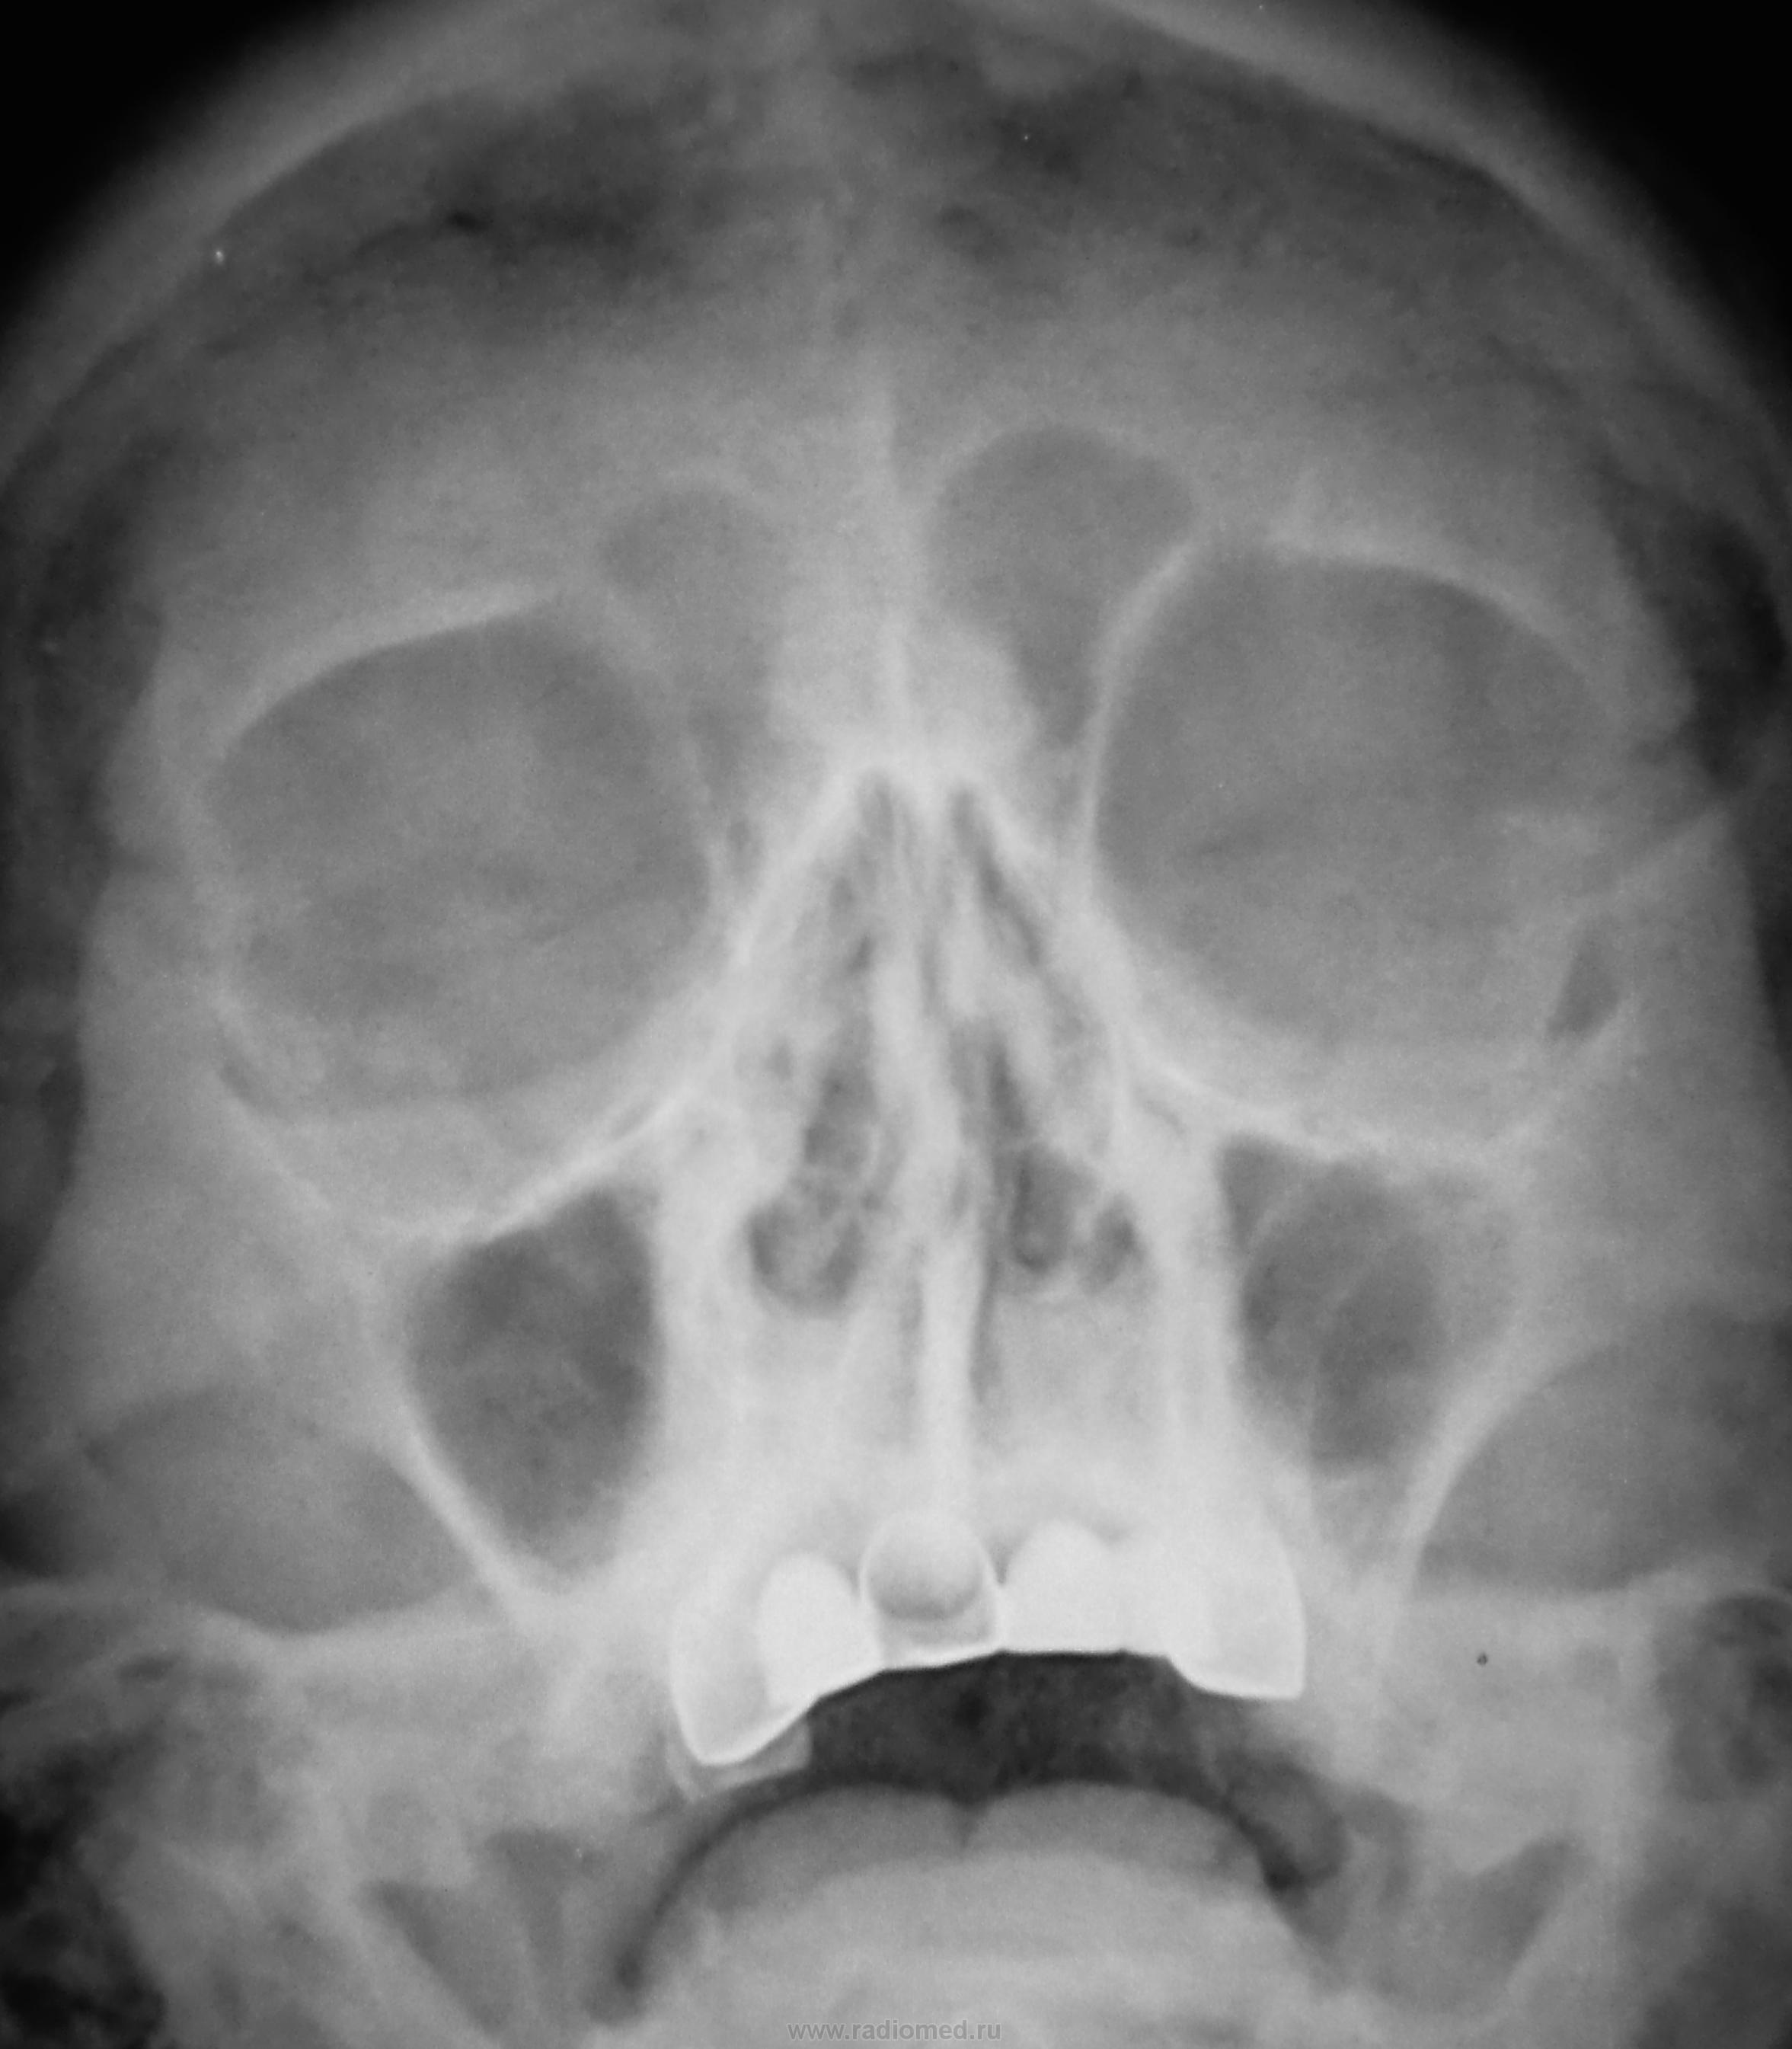

Какие мнения будут по поводу снимка ППН?

Склероз слизистых в\ч пазух (уплотнение и сглаженность внутренних контуров). Вопрос с компактной остеомой в основании срединной перегородки лобных пазух. "Сопли" в носовых ходах с обеих сторон.

По мне - так пневматизация не нарушена.

Перелома в лобно-скуловом сочленении слева не было?

Фиброзирована слизистая обеих гайморовых пазух. Мениск в альвелярной бухте слева на жидкость не похож.

Судя по реконструкции зубо-челюстного ряда, можно предположить одонтогенную природу хронического гайморита.

Есть  искривление  носовой  перегородки smiley. И  мерещится  эндопротез  сосуда  в  проекции  левой  гайморовой  пазухи  и  глазницыblush.

Возможно признаки наличия воспалительного процесса в гайморовых пазухах с экссудативным отделяемым слева. Хммм странно но тоже "мерещится наличие чего то странного в левой пазухе.". Жду ответ.